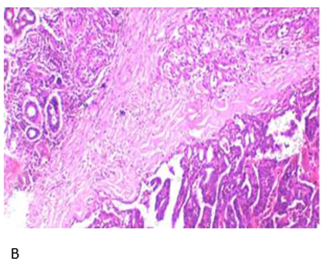

Histopathological

findings from a biopsy of the left retromolar trigone were consistent with CXPA

(Figure 2).

Figure 2. Hematoxylin

and Eosin:A: Low-power view

of salivary gland tissue infiltration by atypical ductal cells forming glands.

Cribriform pattern present; B: High-power view showing capsular invasion by

atypical ductal cells.

Immunohistochemistry

(IHC) findings showed that GFAP was positive in tubules with scattered focal

loss. HMWCK, p63, vimentin, and CK7 were diffusely positive. S100 stained

myoepithelial cells. The MIB1 index was 15-20% on hot spots. Her2-neu was

negative. myoepithelial cells. The MIB-1 index was 15-20 % on hot spots.

Her2/neu was negative. Additionally, the left level IB lymph node biopsy showed

features consistent with a chondroid-forming myoepithelial-rich lesion,

favoring a recurrence of pleomorphic adenoma with extensive myoepithelial

areas.